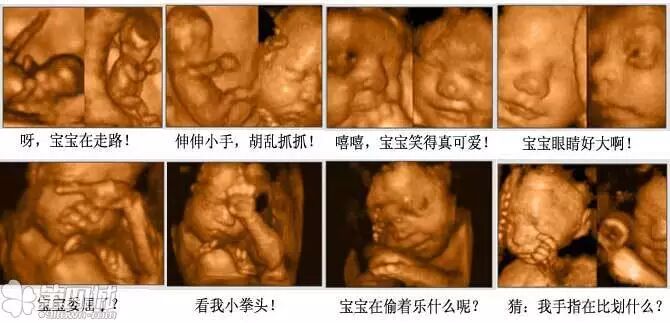

(图片来源网络,仅供参考,不过真实滴彩超图片差不多就是酱紫啦)

最合适打彩超的孕中周期是22周至28周(最佳时间段是24至26周,这个时间段宝宝在子宫里还不算拥挤,面部轮廓清晰,更容易妈、老汉先睹为快看长得像哪个!)

三维彩超是图片,四维彩超是录像(只要医院说可以刻盘的,说明就是四维了哈)